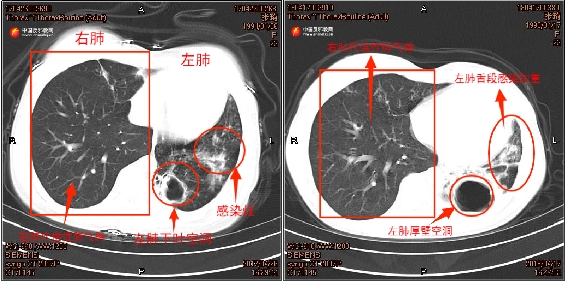

2018年4月第二次确诊肺结核时,张琦的痰培养结果证实其合并烟曲霉菌感染,时任住院医生张洋回忆起当时的治疗困境称:“张琦第二次确诊为复发性耐药肺结核,我们为她制定了针对性治疗方案,并增加了抗真菌的口服药。”治疗期间张琦多次拍摄的胸部CT片,也记录了其左肺病情恶化。张琦左肺下叶空洞逐渐变大,肺叶萎缩,感染逐渐加重。

▲左图为张琦2017年4月胸部CT,右图为张琦2018年4月胸部CT